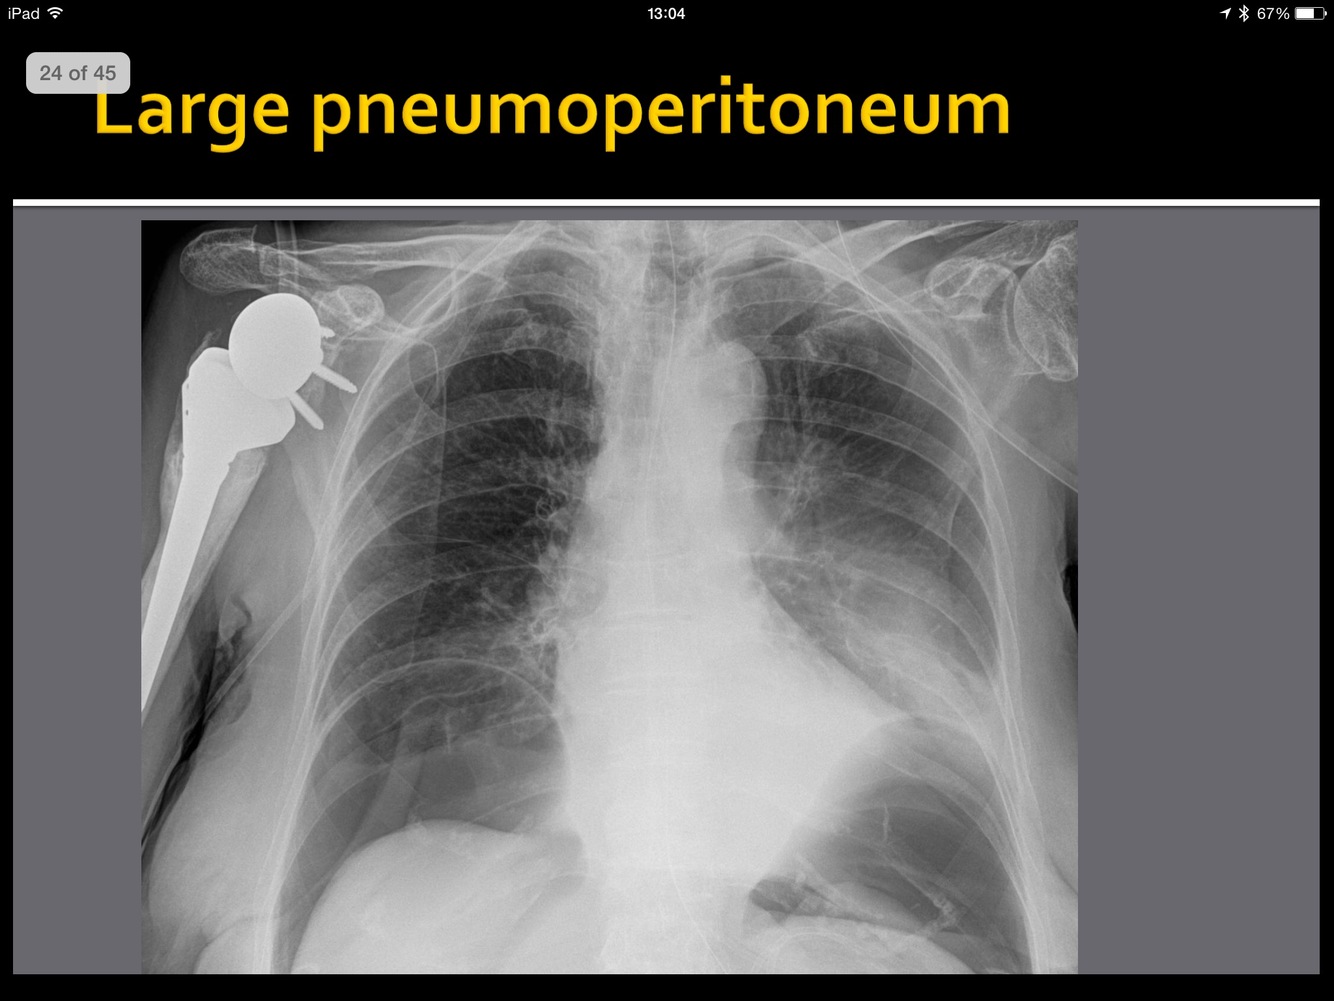

Both SBO and LBO